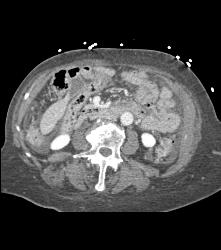

Mesenteric Cyst